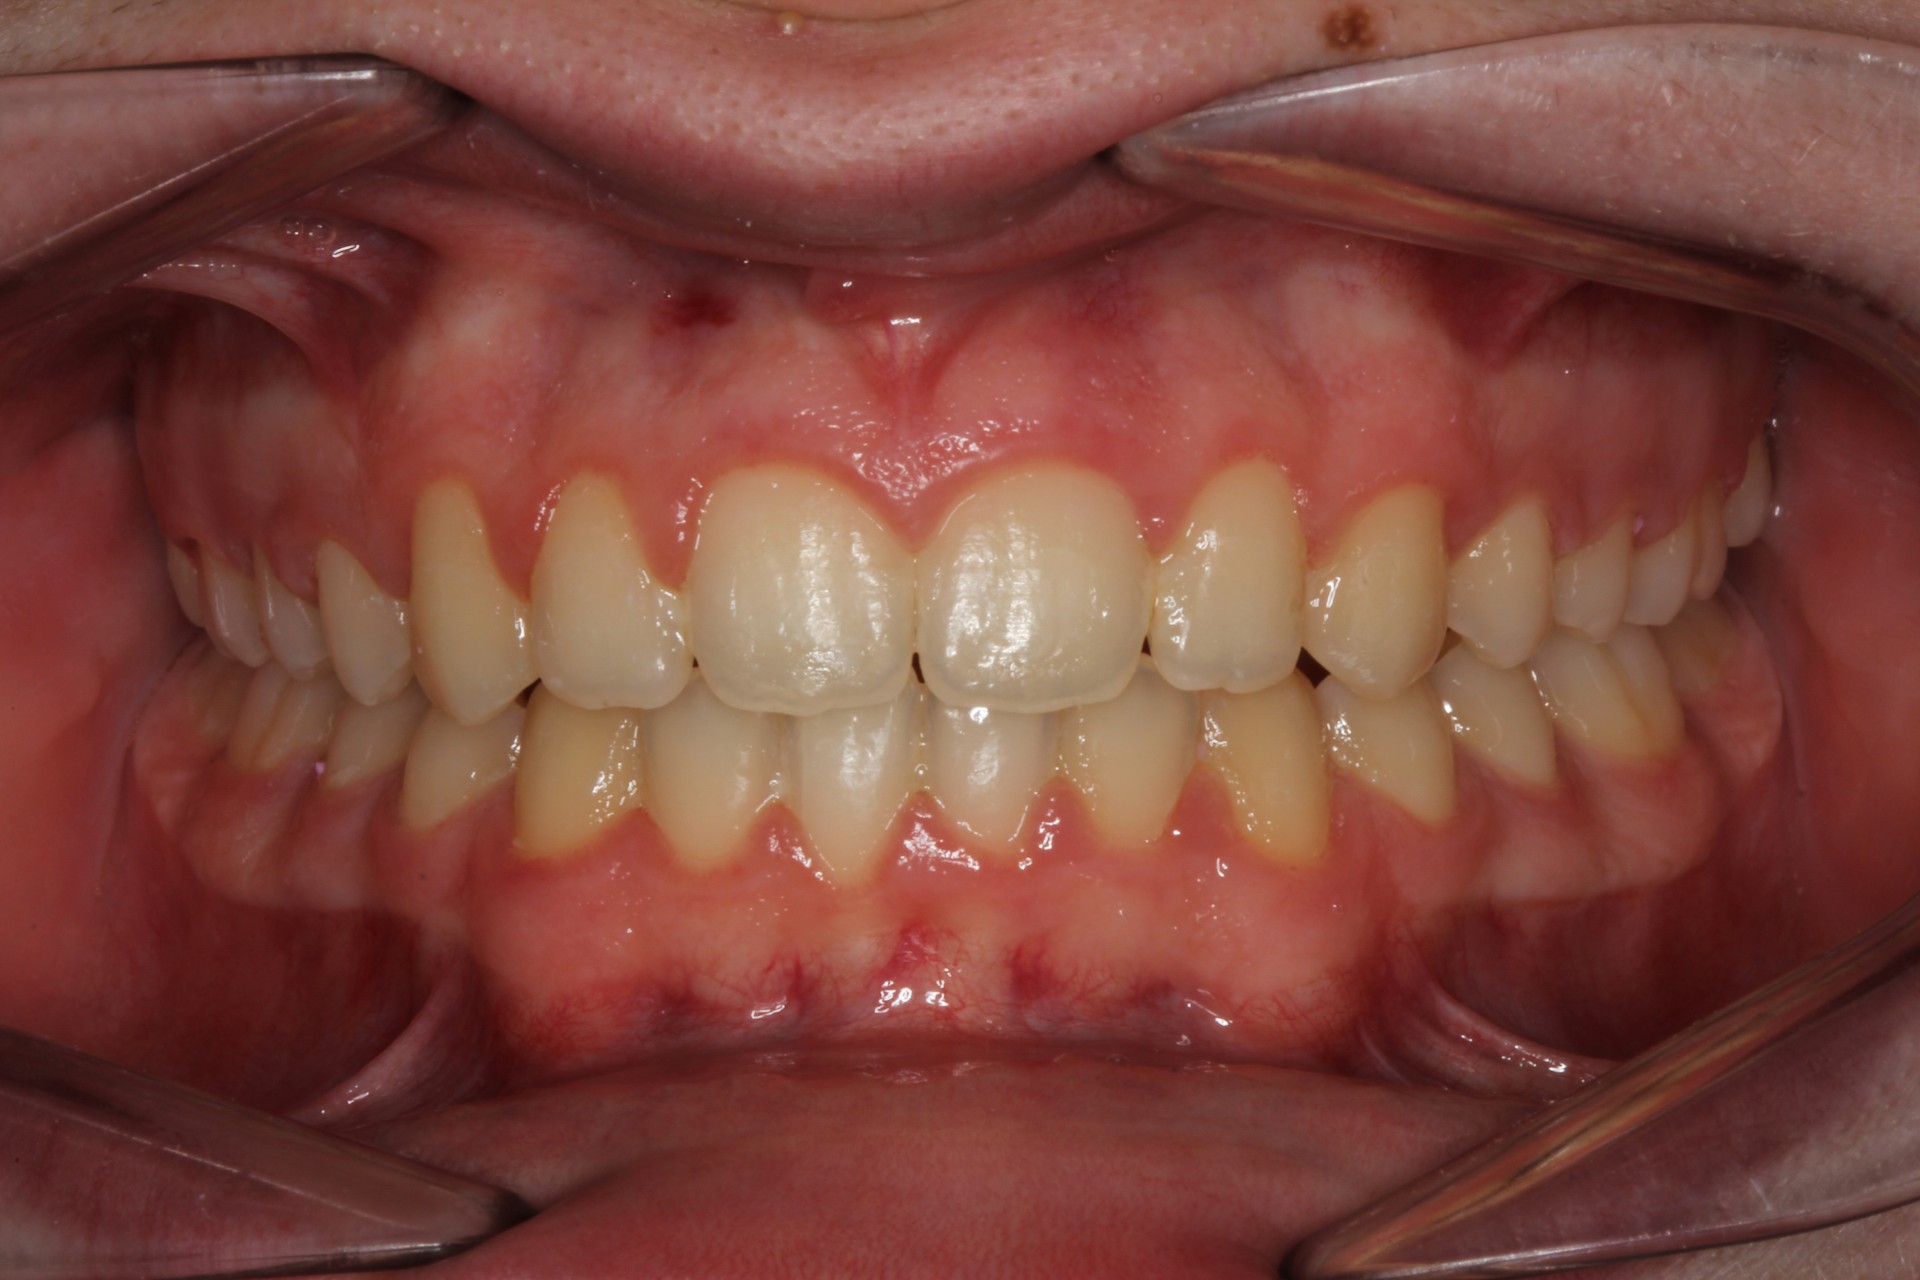

Crowding – Child case